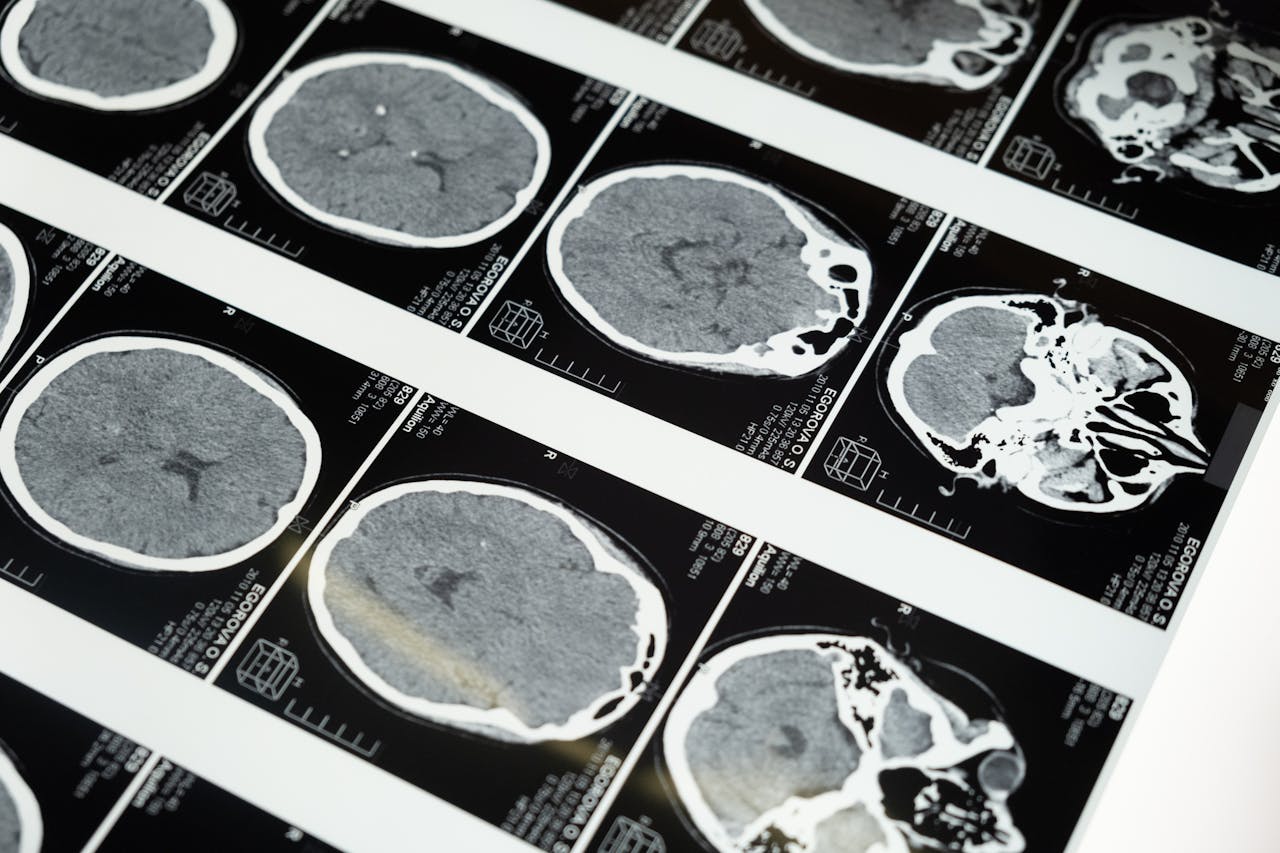

Non-magnetic polymer fasteners are needed in applications where the presence of magnetic materials could interfere with sensitive equipment or processes. In industries like medical imaging (such as MRI machines), aerospace, and electronics, non-magnetic fasteners prevent magnetic fields from disrupting the operation of critical devices. They are also essential in military and defense applications, where magnetic signatures must be minimized for stealth purposes. Additionally, non-magnetic fasteners are used in scientific instruments, data storage, and telecommunications equipment to ensure accurate measurements and reliable performance, as magnetic interference can cause data corruption or operational failures.

Non-magnetic polymer screws, nuts, bolts, washers, and fasteners may be used in a variety of applications where magnetic fields are a concern, such as in the construction of medical equipment or in the assembly of electronic components. They may also be used in the manufacture of non-magnetic materials or in the installation of electrical systems.

In addition to their use in the medical, military, and aerospace industries, non-magnetic polymer fasteners may also be used in other applications where magnetic fields are a concern, such as in the construction of magnetic resonance imaging (MRI) machines or in the operation of military equipment. They may also be used in environments where magnetic materials are not desired, such as in the assembly of scientific instruments or in the transportation of sensitive materials.

Non-magnetic polymer fasteners offer several benefits, including the elimination of magnetic interference, making them ideal for sensitive equipment like MRI machines, aerospace systems, and scientific instruments. They are corrosion-resistant, durable in harsh environments, and lightweight, which is beneficial for reducing system weight in industries like aerospace and automotive. Additionally, these fasteners provide electrical insulation and resist chemicals, ensuring long-term performance in industrial, chemical, and outdoor applications. Their combination of non-magnetic properties, durability, and versatility makes them valuable in environments requiring both reliability and magnetic neutrality.